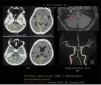

Subarachnoid hemorrhage (SAH) caused by a dissecting aneurysm of the anterior inferior cerebellar artery (AICA) is rare. Partial coil embolization of the AICA may be an effective treatment. A 65-year-old woman presented at the emergency room with headache and vomiting for the past five days, after contracting coronavirus disease (COVID-19). Computed tomography (CT) revealed SAH and intraventricular hemorrhage, and the patient was diagnosed with a dissecting aneurysm of the AICA. The patient underwent endovascular surgery, and the AICA was partially occluded using coiling, with no subsequent hearing disturbance, cranial nerve palsy, or infarction. Ventriculoperitoneal shunt surgery was performed for hydrocephalus at 7weeks after SAH. The patient was discharged from hospital with no neurological deficit. We reported a rare case of ruptured AICA dissecting aneurysm, which was treated by partial coil embolization without neurological deficit or infarction.